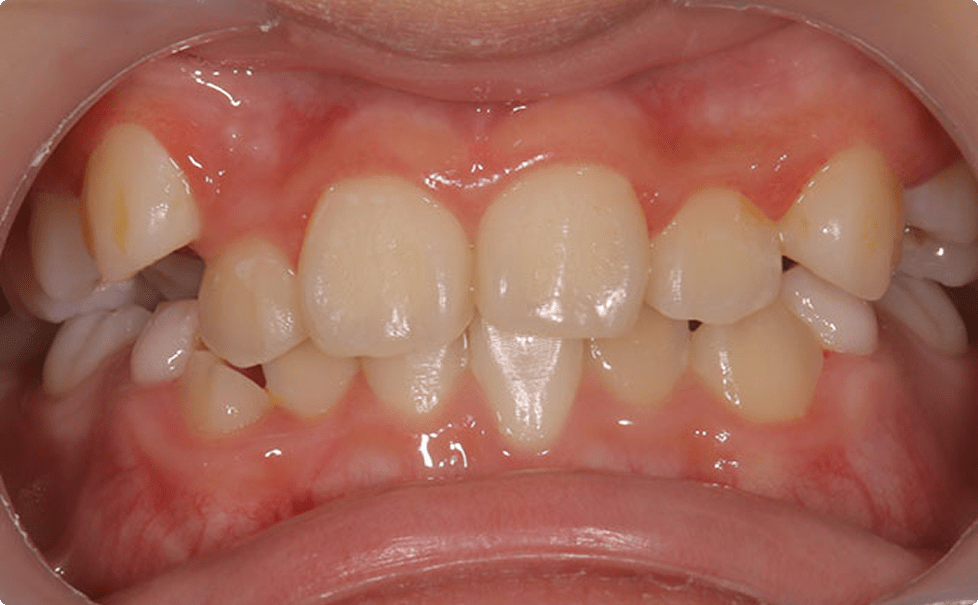

症例3:叢生の矯正治療

BEFORE

AFTER

症例概要

年代・性別

10歳代 女性

主訴

歯並びを良くしたい

治療内容

ブラケット(ワイヤー)を用いた矯正治療

治療期間

4ヶ月

治療のリスク

定期検診、セルフケアを怠ると虫歯になる可能性があります

治療費用

440,000円(税込)